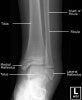

소아 발목의 X-ray2017-02-26카테고리 103원본 보기 Ankle Paediatric Protocol : AP, Lateral Ankle AP view Ankle Mortise view Ankle Lateral view ← 이전 글소아 무릎, 아래 다리의 X-ray다음 글 →발목관절 골절(Salter-Harris fracture)같은 카테고리 글2017-02-25소아 무릎, 아래 다리의 X-ray2017-02-18소아의 골반, 고관절, 대퇴골의 X-ray2017-02-14손목 성장판 골단판 골절(Epiphysiolysis fracture)← 전체 글로 돌아가기